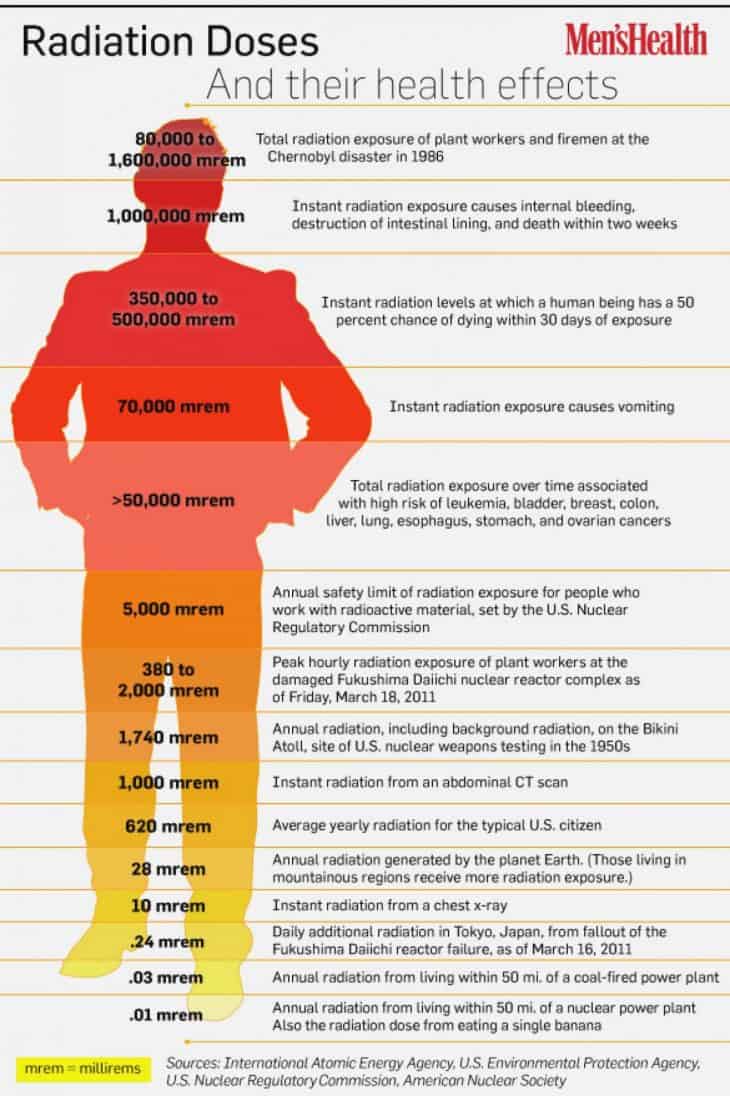

This principle confers to physicians the responsibility for reducing as much as possible the dose of radiation during cardiovascular procedures to minimize the. Radiation exposure can be accumulated over the time of. We strive to perform only tests that are necessary and to use just enough radiation doses to provide a high quality image to help your.

There are various types of shielding used in the reduction of radiation exposure including lead aprons, mobile lead shields, lead glasses, and lead barriers. The purpose of this article is to (a) describe the importance of educating radiology personnel, patients, and referring clinicians about the concerns over ct radiation, (b). Every diagnostic medical procedure involving ionizing radiation needs to minimize radiation exposure without compromising the benefit for the patient.

Steps we take to minimize radiation. Time, distance, and shielding measures minimize your exposure to radiation in much the same way as they would to protect you against overexposure to. Time, distance, and shielding actions minimize your exposure to radiation in much the same way as they would to protect you against overexposure to the sun: